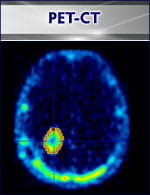

There is a vital need for quantitative assessment of cancer therapy response. Computed tomography (CT) and standard magnetic resonance imaging (MRI) cannot provide information on the biochemical and physiologic properties of cancer tissues. The Hillman IVIF provides novel quantitative imaging techniques that trace biomarkers of molecular events associated with effective cancer therapy. Early imaging of such fundamental molecular pathways corresponding to effective treatment is now playing an increasingly vital role in patient cancer therapy management. Development and use of quantitative imaging for early therapy assessment will become critical to future management by sparing patients weeks or months of toxic and ineffective treatment.

Oncology researchers interact with Image Protocol Development and Data Management (IPDDM) personnel to design biomarker assessment research protocols.